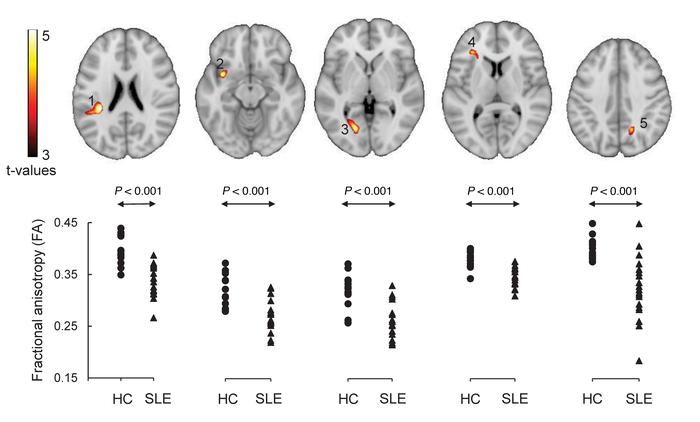

Regions with abnormal microstructure in SLE subjects.

Significant reductions (P < 0.001) in FA were present in the following brain areas (top): 1, white matter tracts in the parietal lobe, a part of the superior longitudinal fasciculus (SLF); 2, white matter tracts in the vicinity of the insular, a part of the uncinate fasciculus (UF); 3, white matter tracts in the occipital lobe/cingulum (hippocampus); 4, white matter tracts in the frontal lobe, a part of the inferior frontal occipital fasciculus (IFOF); and 5, white matter tracts in the parietal lobe, a part of the splenium of corpus callosum (CC). Individual cluster fractional anisotropy (FA) values for the SLE and control groups were plotted (bottom). All group differences were highly significant (P < 0.001). The details of these brain regions were presented in Table 4.